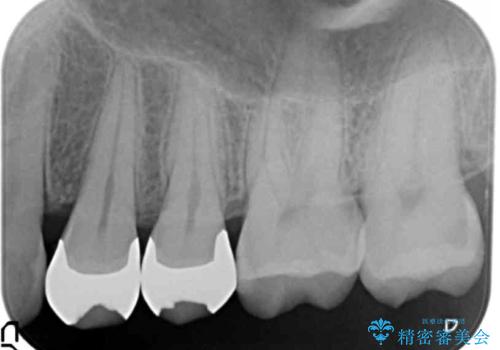

- 口の中に見える銀歯を、金属アレルギーの対策と審美性の向上のため全て除去したい!と希望され来院されました。

銀歯を丁寧に除去したのち、精度の良いセラミックインレー、セラミッククラウンで修復・補綴処置を行っていきます。

- 62.7万円(ジルコニアクラウン×3・仮歯×3・セラミックインレー×3)費用は治療当時の料金となります